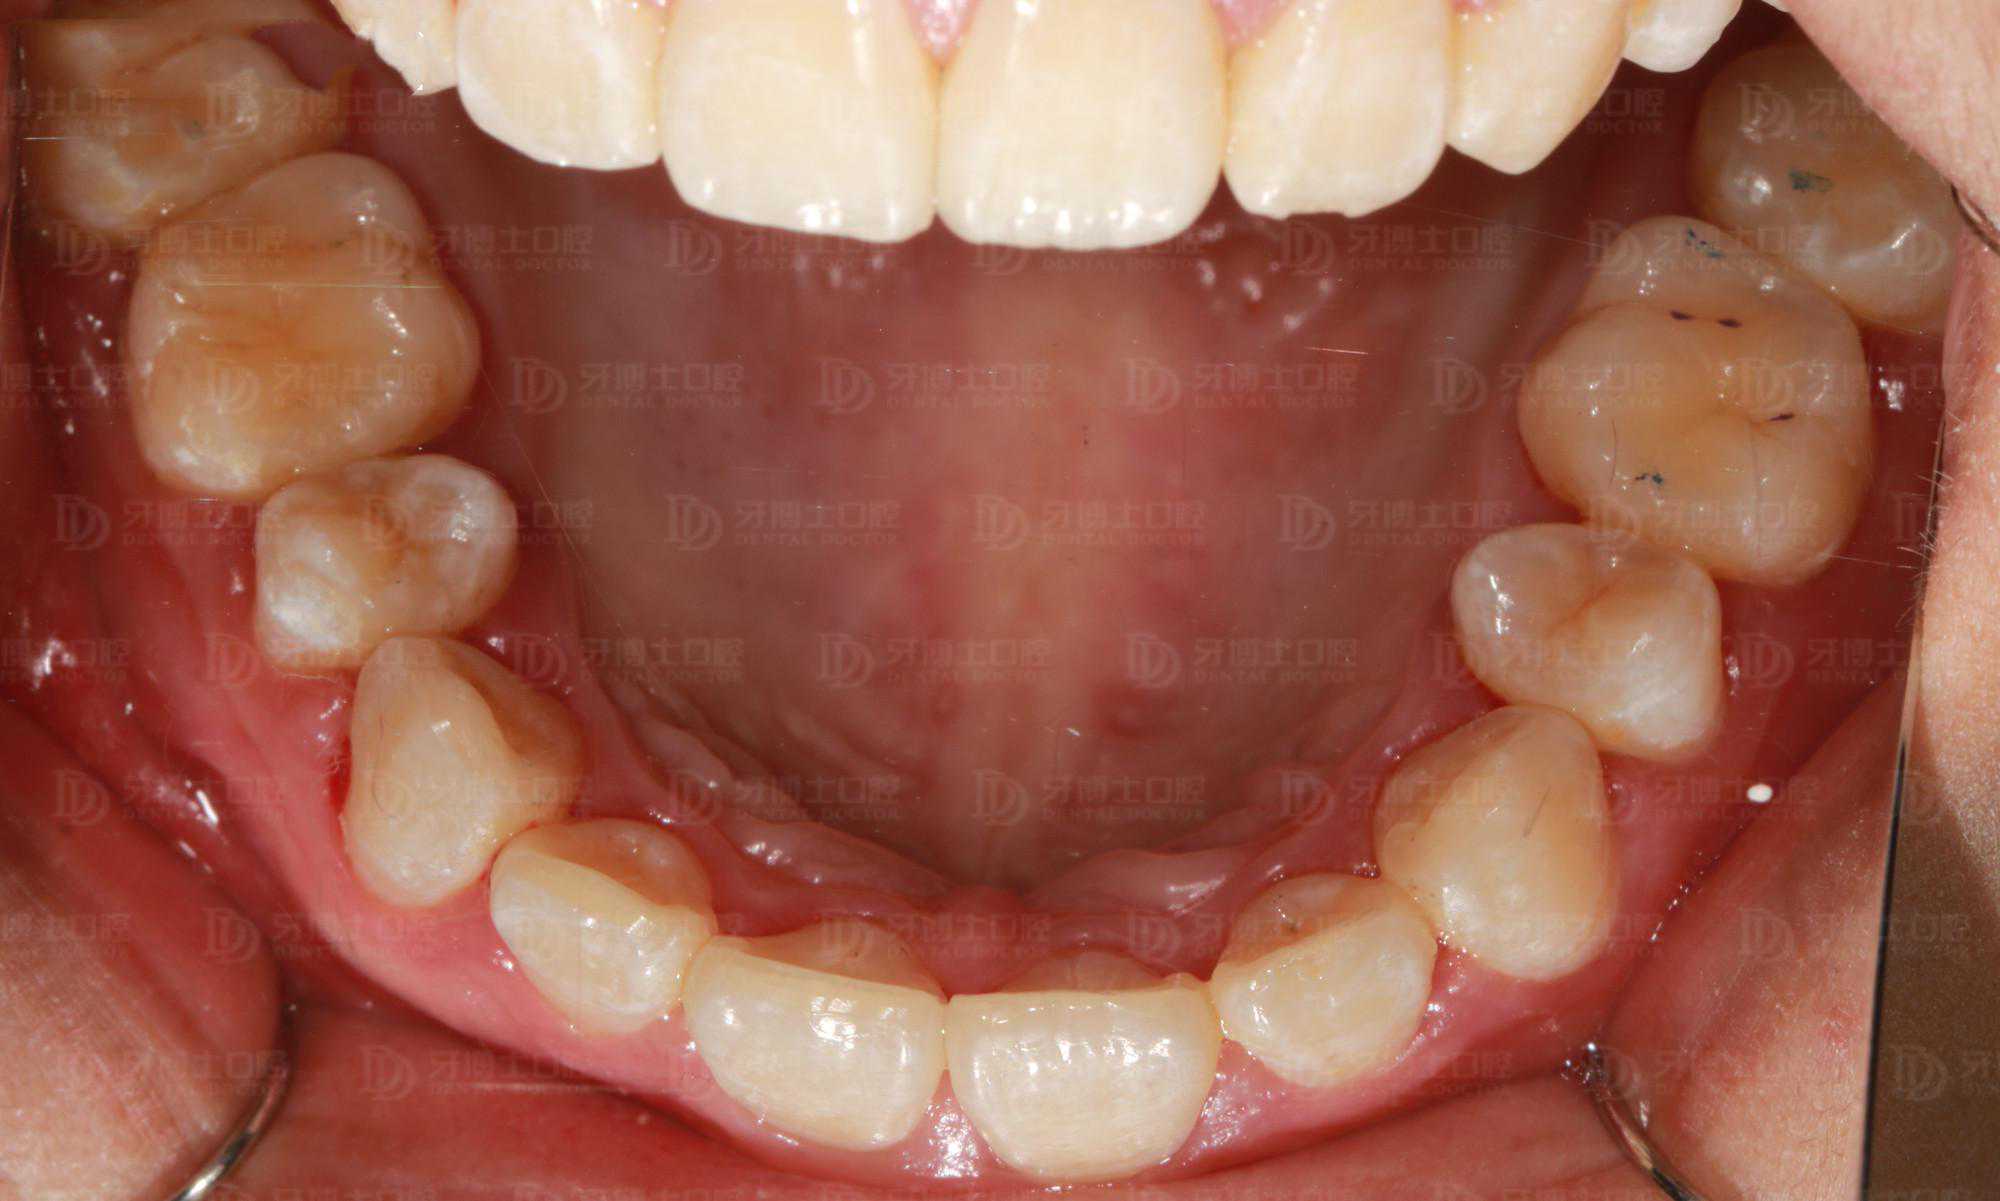

牙齿情况:深覆盖深覆颌

矫正前牙列不齐,并有牙龈炎、牙结石,刷牙时会出血,同时美观度较差,影响容貌。

牙齿排齐内收,更易清洁了,牙周问题明显改善很多,面部整体美观度增加,笑容更加自信。